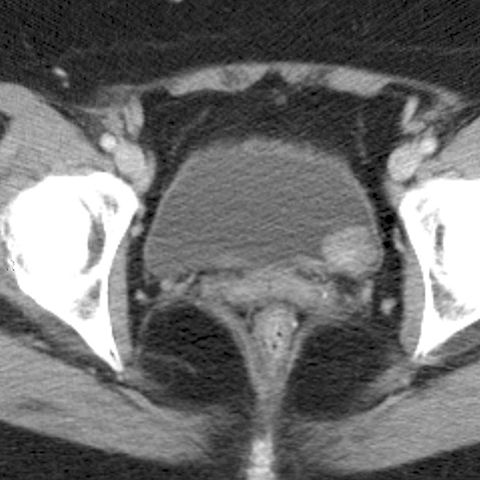

Bladder cancer, non-enhanced CT [1 of 2]